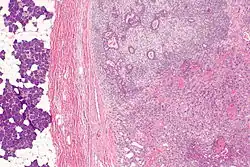

Carcinoma ex pleomorphic adenoma

| Micrograph of a carcinoma ex pleomorphic adenoma. The carcinoma component is on the lower right of the image. Benign parotid gland is seen at the left and pleomorphic adenoma is seen at the upper right. H&E stain. | |

Carcinoma ex pleomorphic adenoma (ca ex PA) is a type of cancer typically found in the parotid gland. It arises from the benign tumour pleomorphic adenoma.

Carcinoma ex pleomorphic adenoma is diagnosed by examining it under the microscope with consideration of the individual history.